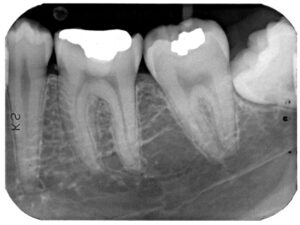

We are delighted to welcome you to our practice and are pleased that you chose us to serve your dental needs.